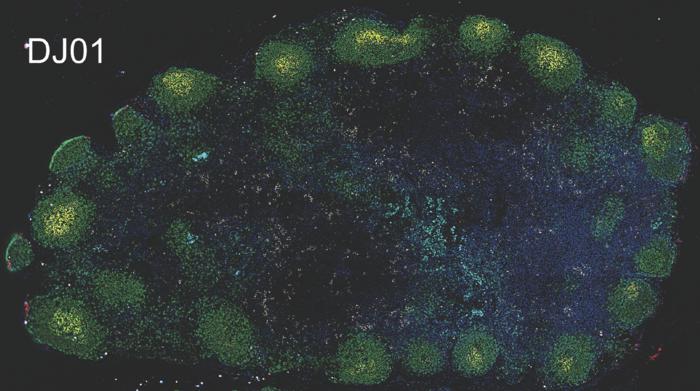

Dr. Ling and her team used several advanced genetic tools and sequencing techniques to track the virus. They teamed up with Brandon Keele, PhD, at the AIDS and Cancer Virus Program at Fredrick National Laboratory, who generated barcoded viruses. More than 9,000 individual viruses in the stock have unique genetic barcodes, “like when you go to Walmart and each item has its unique barcode to scan,” Dr. Ling explains.

Those barcoded viruses were given to seven nonhuman primates. After infection was established, the primates began receiving antiretroviral therapy. After four to six months on ART, the animals had either very small amounts or no detectable virus circulating in blood, much like people living with HIV who are on ART. When treatment was stopped after more than a year of ART, researchers were able to assess the very earliest stages of viral rebound.

Thanks to the barcoded viruses, they could identify in which tissues the virus had replicated the fastest and spread the furthest just seven days after treatment was stopped. They matched the barcodes most prevalent in blood plasma to the barcodes detected in specific tissues. Notably, the standard test did not detect any virus in blood at the seven-day mark – the amounts present were too low to be detected – but more sensitive deep sequencing did.

The researchers found three leading contributors: mesenteric lymph nodes, which are found in the tissue connecting the intestines to the abdominal wall; the spleen, which is a part of the lymphatic system that filters blood; and inguinal lymph nodes, which are located in the groin.

Through additional analyses, the researchers found CD4 T cells, a type of immune cell, in the mesenteric lymph nodes and spleen had higher amounts of intact virus and replication activity, which corresponded with higher rates of barcoded viruses from those regions in blood plasma. This was further confirmed using a novel technology by Qingsheng Li, PhD, at University of Nebraska-Lincoln.